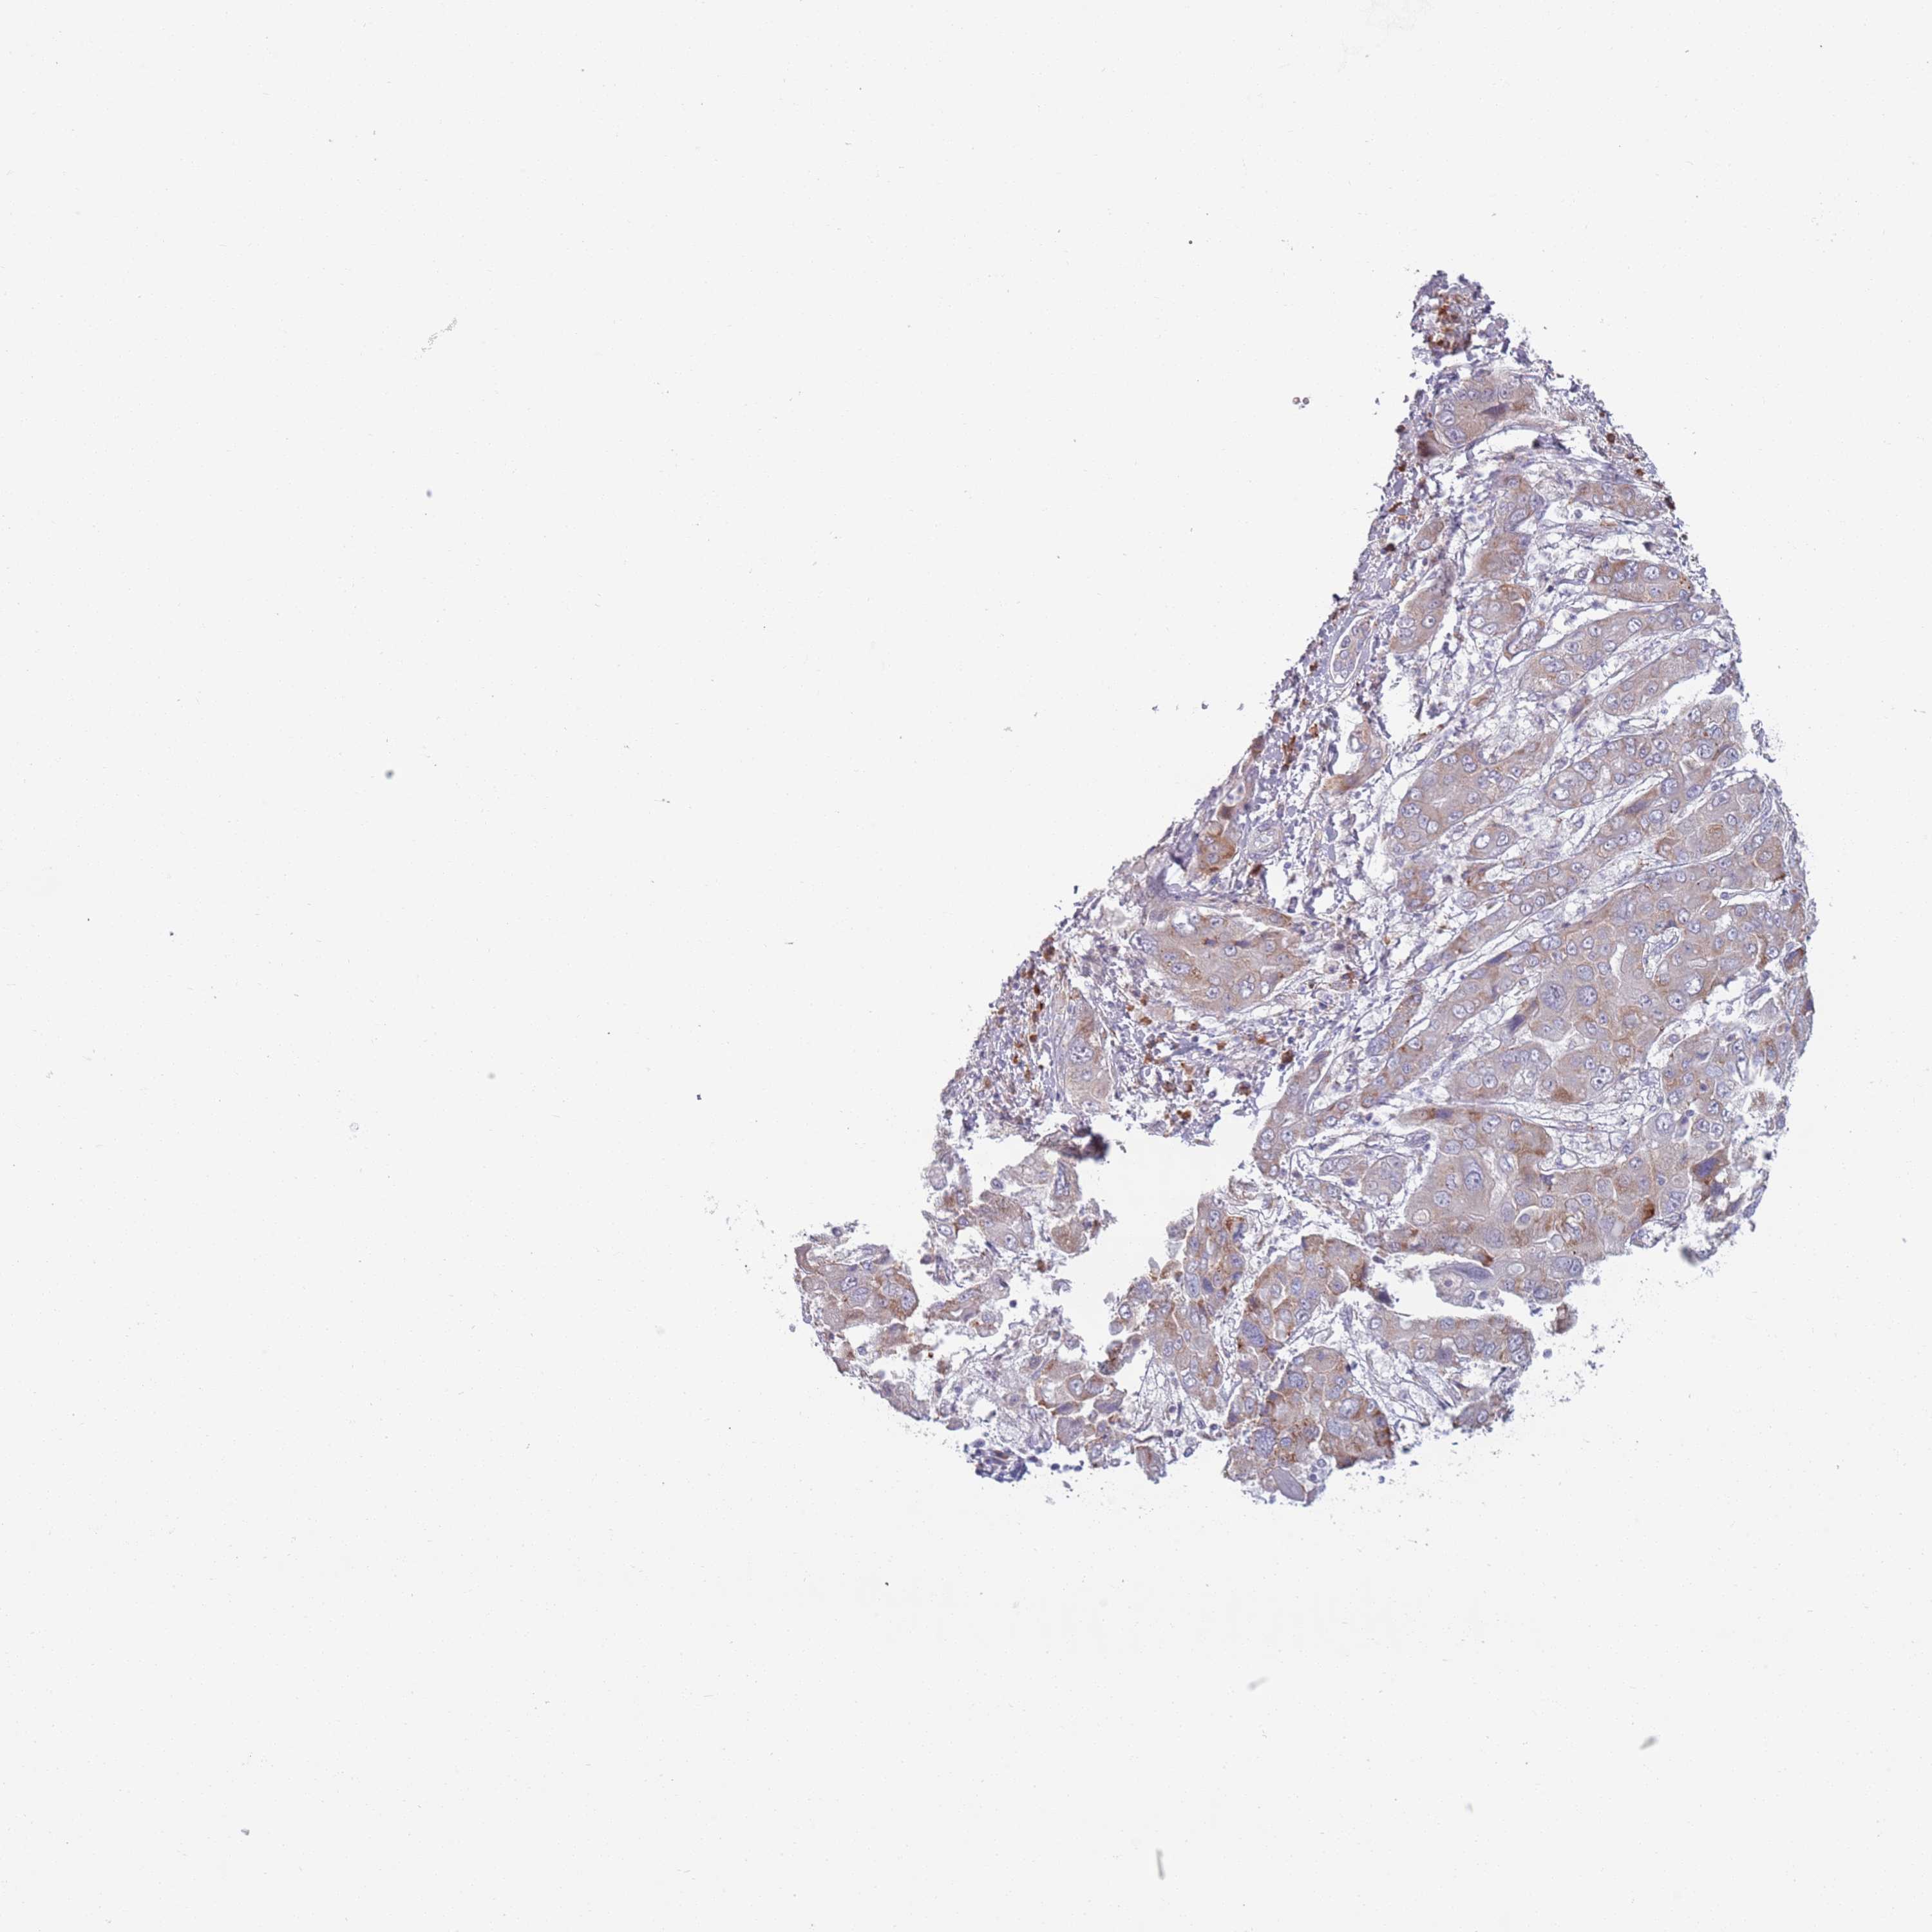

LIVER CANCER - Protein expressioni

A mouse-over function shows sample information and annotation data. Click on an image to view it in a full screen mode. Samples can be filtered based on level of antibody staining by selecting one or several of the following categories: high, medium, low and not detected. The assay and annotation is described here.

Note that samples used for immunohistochemistry by the Human Protein Atlas do not correspond to samples in the TCGA dataset.

Antibody stainingi

Antibody staining in the annotated cell types in the current human tissue is reported as not detected, low, medium, or high, based on conventional immunohistochemistry profiling in selected tissues. This score is based on the combination of the staining intensity and fraction of stained cells.

Each image is clickable and will lead to virtual microscopy that enables deeper exploration of all samples and also displays staining intensity scores, fraction scores and subcellular localization as well as patient and tissue information for each sample.

Antibody HPA048884

Staining

High

Medium

Low

Not detected

Intensity

Strong

Moderate

Weak

Negative

Quantity

>75%

75%-25%

<25%

None

Location

Nuclear

Cytoplasmic/membranous

Cytoplasmic/membranous,nuclear

Cholangiocarcinoma

Carcinoma, Hepatocellular, NOS